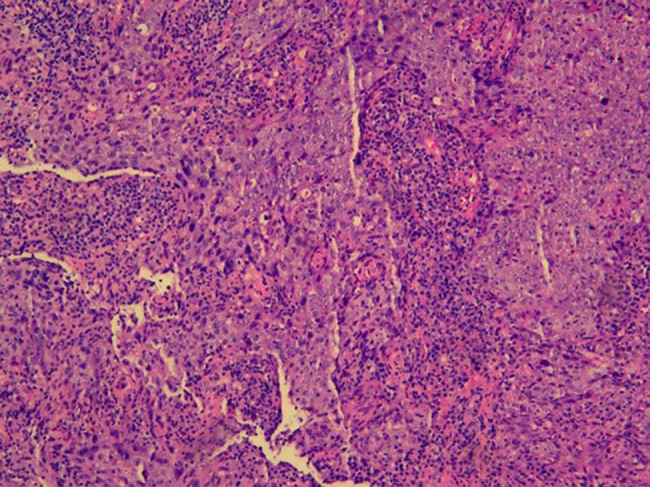

严重再生障碍性贫血(SAA)和鼻咽癌(NPC)是两种不同的疾病,如果不及时治疗,将危及生命。SAA和NPC同时发生是罕见的,并且呈现出一个复杂的治疗悖论。本研究报告了一个诊断为SAA和NPC的独特病例。患者最初接受单倍体造血干细胞移植(HSCT)以实现血液系统快速恢复,随后接受尼莫单抗+放疗治疗癌症。该病例提示,序贯单倍体HSCT和放疗可能是同时存在SAA和NPC患者的一种有希望的治疗策略。

Severe aplastic anemia (SAA) and nasopharyngeal carcinoma (NPC) are two different diseases and are life-threatening if left untreated. The co-occurrence of SAA and NPC is rare and presents a complex therapeutic paradox. This study reports a unique case of a patient diagnosed with both SAA and NPC. The patient initially underwent haploidentical hematopoietic stem cell transplantation (HSCT) to achieve rapid hematologic recovery, followed by nimotuzumab + radiotherapy for carcinoma treatment. This case suggests that sequential haploidentical HSCT and radiotherapy may represent a promising therapeutic strategy for patients with coexisting SAA and NPC.